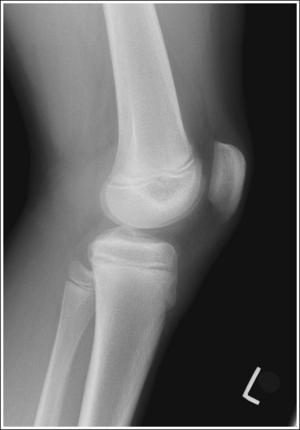

See Figures 6-80 and 6-81 and Box 6-17.

Contrast and density are adequate to demonstrate the suprapatellar fat pads.

• Suprapatellar fat pads. Two soft tissue structures of interest at the knee are used to diagnose joint effusion and knee injury. They are the posterior and anterior suprapatellar fat pads. Both are located anterior to the patellar surface of the distal femur and are separated by the suprapatellar bursa (Figure 6-82). Fluid that collects in the suprapatellar bursa causes the anterior and posterior suprapatellar fat pads to separate. It is a widening of this space that indicates a diagnosis of joint effusion.

The patella is situated proximal to the patellar surface of the femur, and the patellofemoral joint is open.

• The knee should be flexed 10 to 15 degrees. With less than 20 degrees of knee flexion, the patella is situated proximal to the patellar surface of the femur, the quadriceps are relaxed, and the patella is fairly mobile. In this patellar position the anterior and posterior suprapatellar fat pads can be easily used to evaluate knee joint effusion. Conversely, when the knee is flexed 20 degrees or more, a tightening of the surrounding knee muscles and tendons is present, the patella comes into contact with the patellar surface of the femur, and the anterior and posterior suprapatellar fat pads are obscured, eliminating their usefulness in diagnosing joint effusion (see Image 67). Some authors indicate that 20 to 30 degrees of knee flexion should be used on a lateral knee projection. Facility routines dictate the actual number of degrees that should be used.

The distal articulating surfaces of the medial and lateral femoral condyles are superimposed, and the knee joint space is open.